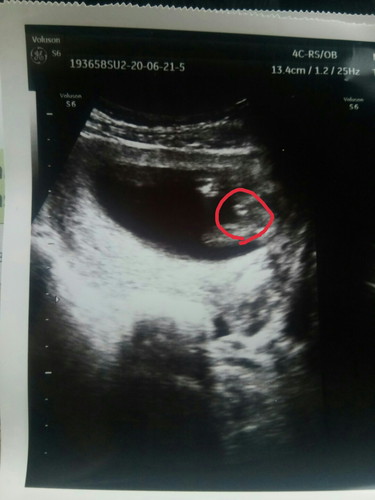

หมอบอกว่าน่าจะเป็นผู้ชาย 15+6d เห็นไข่น้องชัดขนาดนี้แล้วเหรอคะ แม่ๆช่วยยืนยันหน่อย 😆

12วีคก็เริ่มตรวจเจอแล้วค่ะ อันนี้ตั้ง15วีคละ

ชายจะเห็นไวกว่า ญ ค่ะ ของเรานี่ก็ซาวตอน 15w

ถ้าจะให้ชัวร์รอสัก18วีคขึ้นไปค่ะแม่